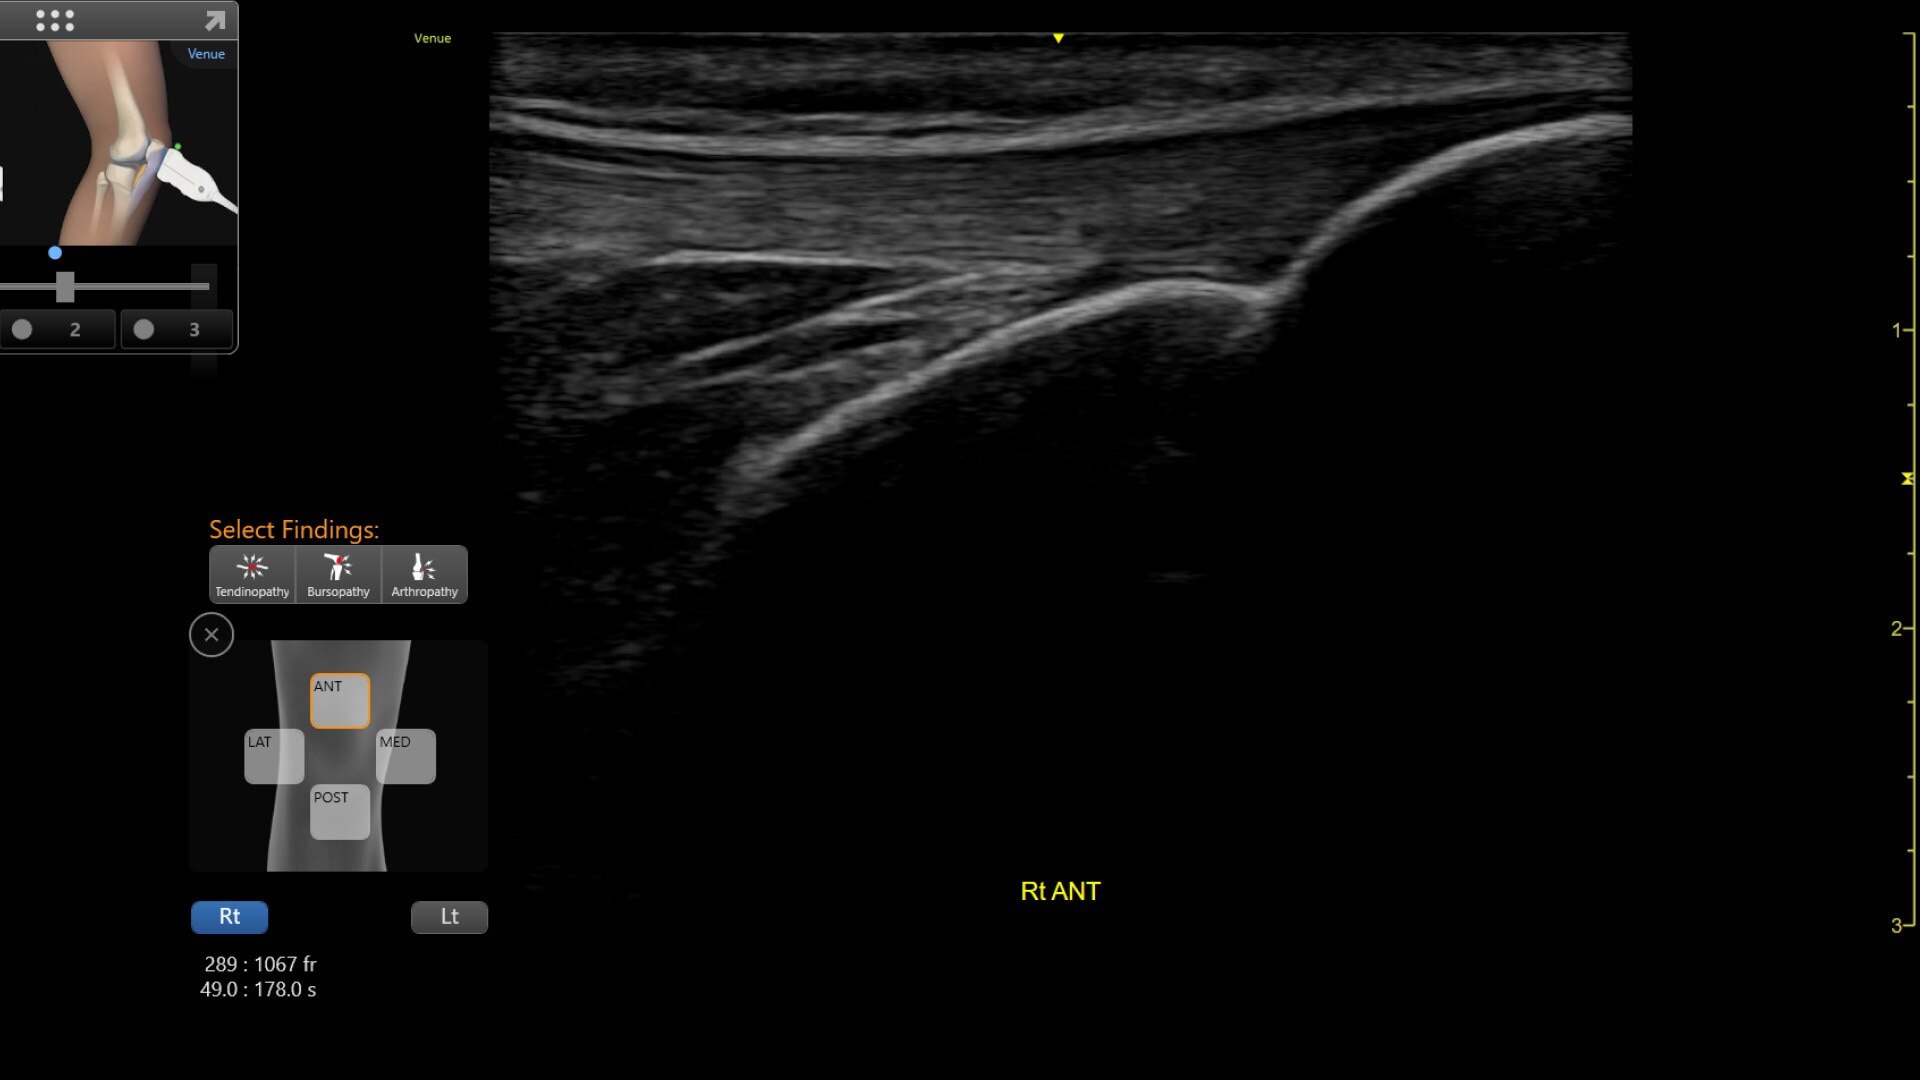

Venue Coach MSK

Simplifying MSK scans

This easy-to-use exam documentation tool assists users through exams by providing reference images and anatomy markups. Multiple anatomical areas and helpful video tutorials help clinicians to acquire the scans they need.

MSK Diagrams: Simplifies documentation and assists the clinician in follow up for patients. No need to manually type findings—you can simply assign a label from a pre-populated list that correlates with the images. Get a single view diagram with one click image storing, keep track of assessments and show trends in response to therapy.

Reference Image: Reference image provides anatomy mark-ups to assist novice users in scanning the correct anatomy

Bilateral mode: Helps you to view the opposite side of the same zone for comparison (available for Shoulder preset)